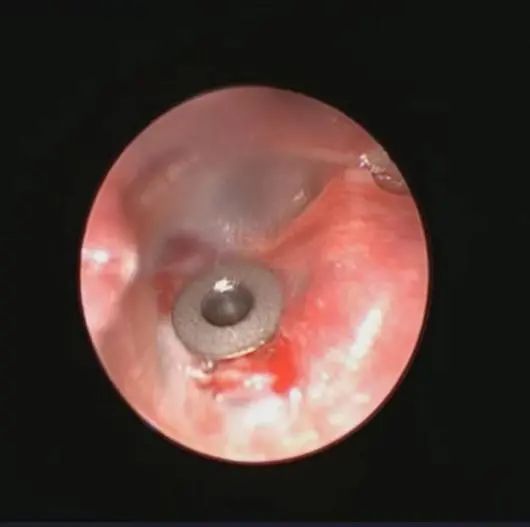

安女士的手术当中,鼓膜开窗后,从鼓室里冲洗出大量咖啡色的积液,冲洗完后,鼓膜植入通风管,安女士耳闷塞感立马就得到了缓解,听力也提高了,整个人清清爽爽、开开心心地回去上班了。

患者鼓膜置管后。